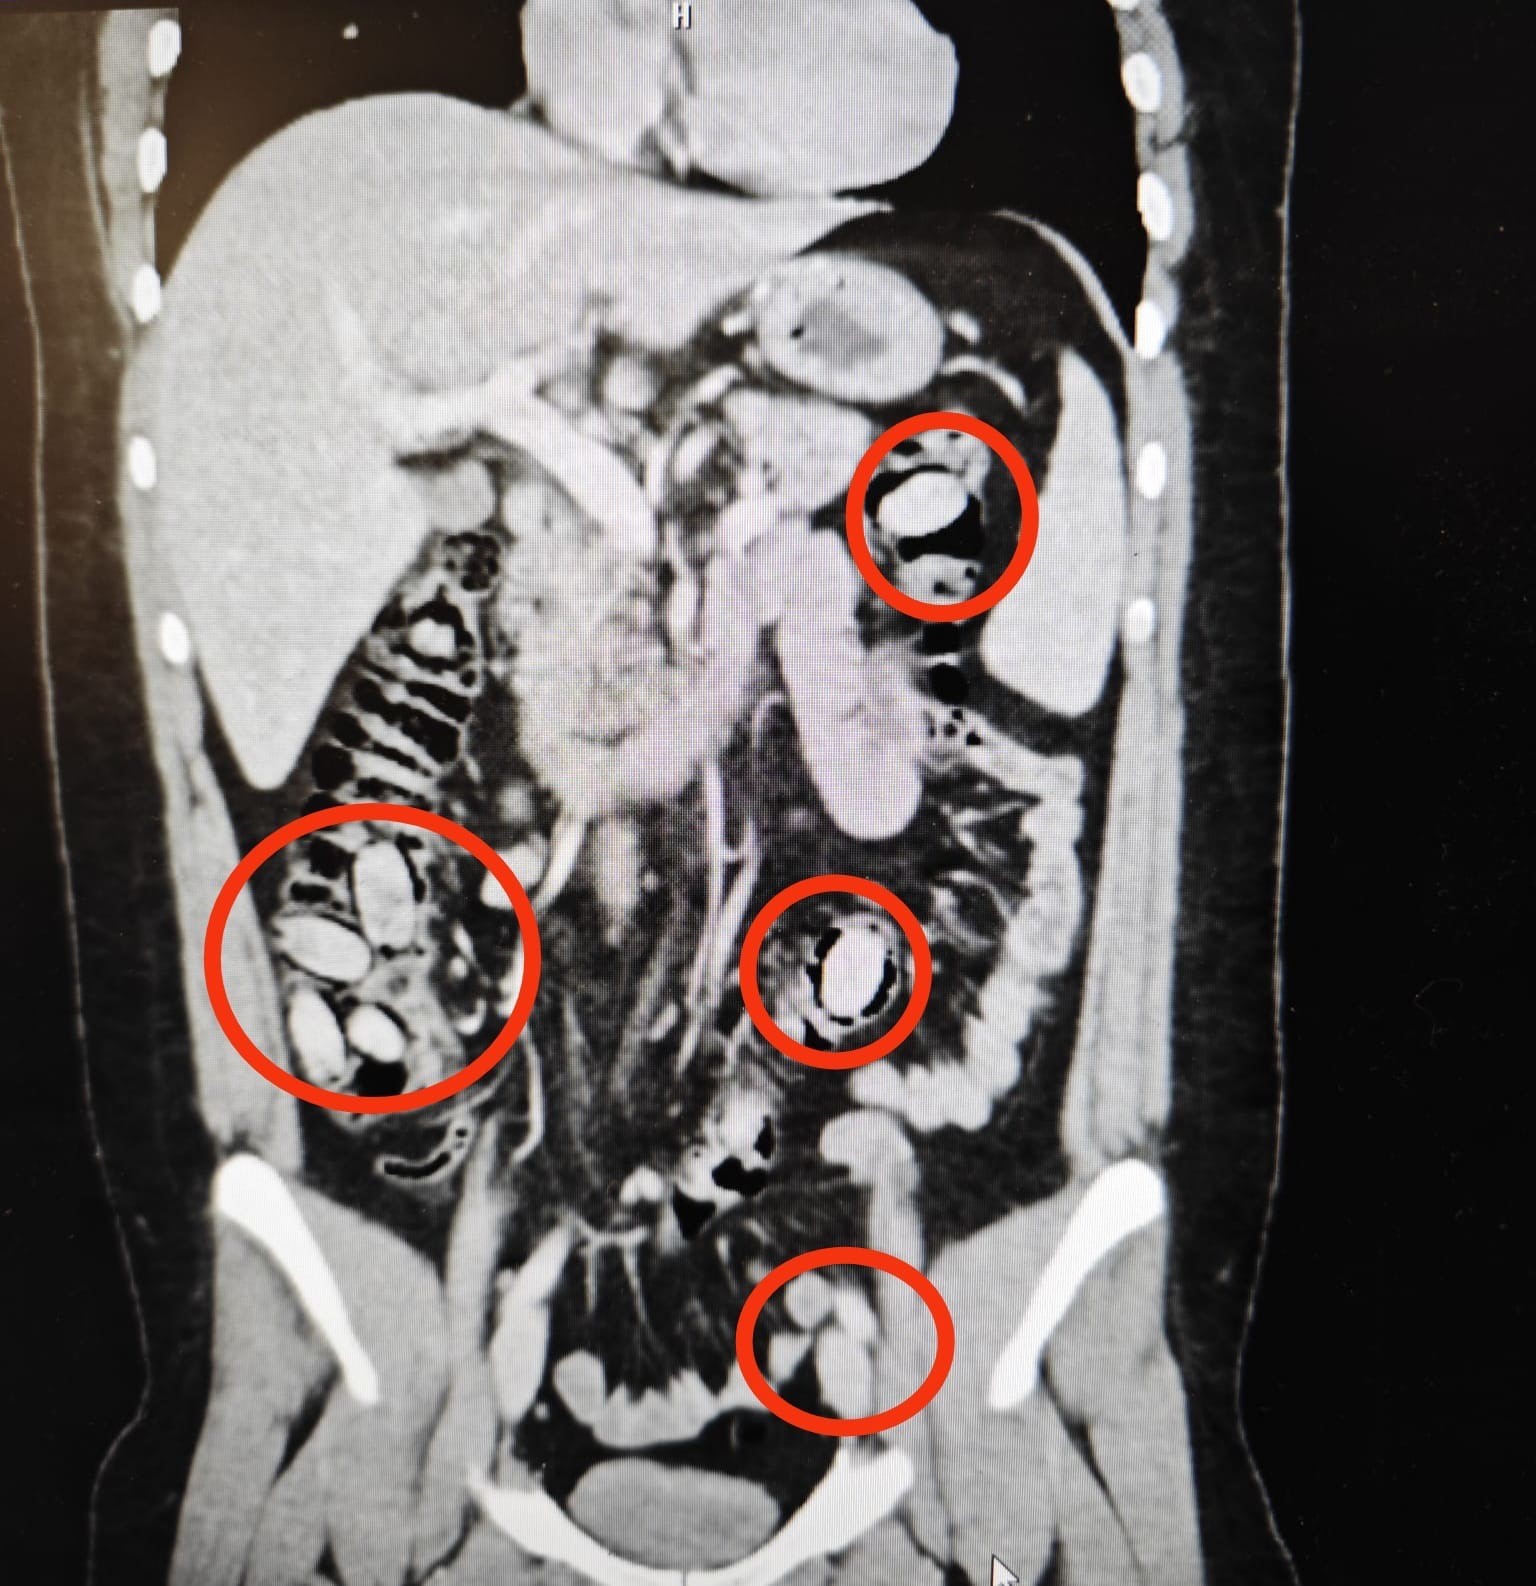

Edinilen bilgiye göre, yurtdışından Eskişehir’e gelen S.A. (25) isimli yabancı uyruklu şahıs, kent girişindeki uygulama noktasında polis ekiplerinin şüphesi üzerine durduruldu. Şahsın durumundan şüphelenen ekiplerce hastaneye sevk edilen S.A.’ya yapılan detaylı tetkiklerde, yutmak suretiyle midesinde 44 kapsül metamfetamin maddesi taşıdığı tespit edildi.

Cerrahi müdahale ile uyuşturucu maddeler şahsın midesinden çıkarıldı. Tedavisinin ardından adliyeye sevk edilen S.A., çıkarıldığı mahkemece tutuklanarak cezaevine gönderildi.